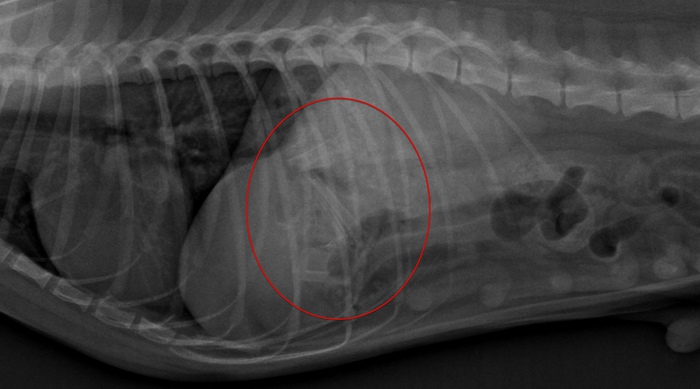

(レントゲン画像:胃内に多数の骨が映っております)

予想以上に骨以外の食さが多く、骨と食さとの見分けがつきにくい中での作業となりました。また、食べた骨の本数も形状も分からないので、どれくらい取ればよいのか、逐一レントゲンを撮りながらの作業となりました。